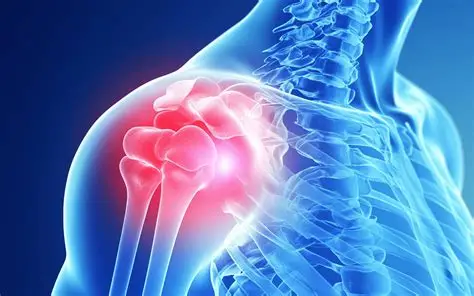

Shoulder Dislocation